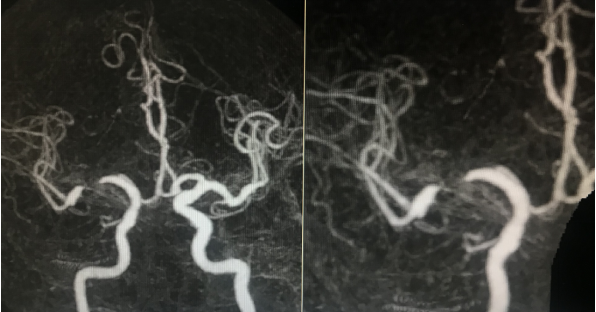

手术前检查:

2019-5-15 CTA提示右侧MCA-M1段重度狭窄,狭窄远端近分叉部血管略有扩张

血管造影显示右侧MCA重度狭窄,近端血管直径3mm,紧邻狭窄远端 2.8mm,远端近分叉部直径3.8mm